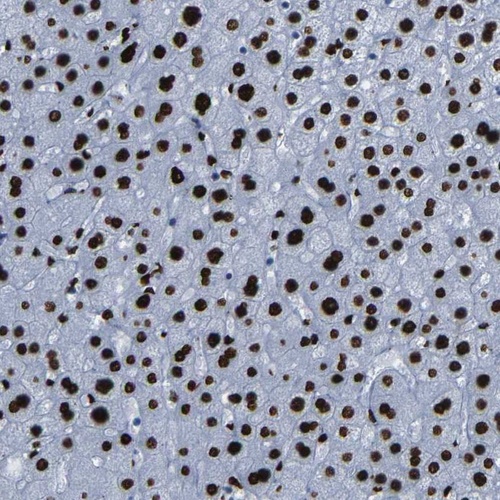

Immunohistochemical staining of human liver shows strong nuclear positivity in hepatocytes.